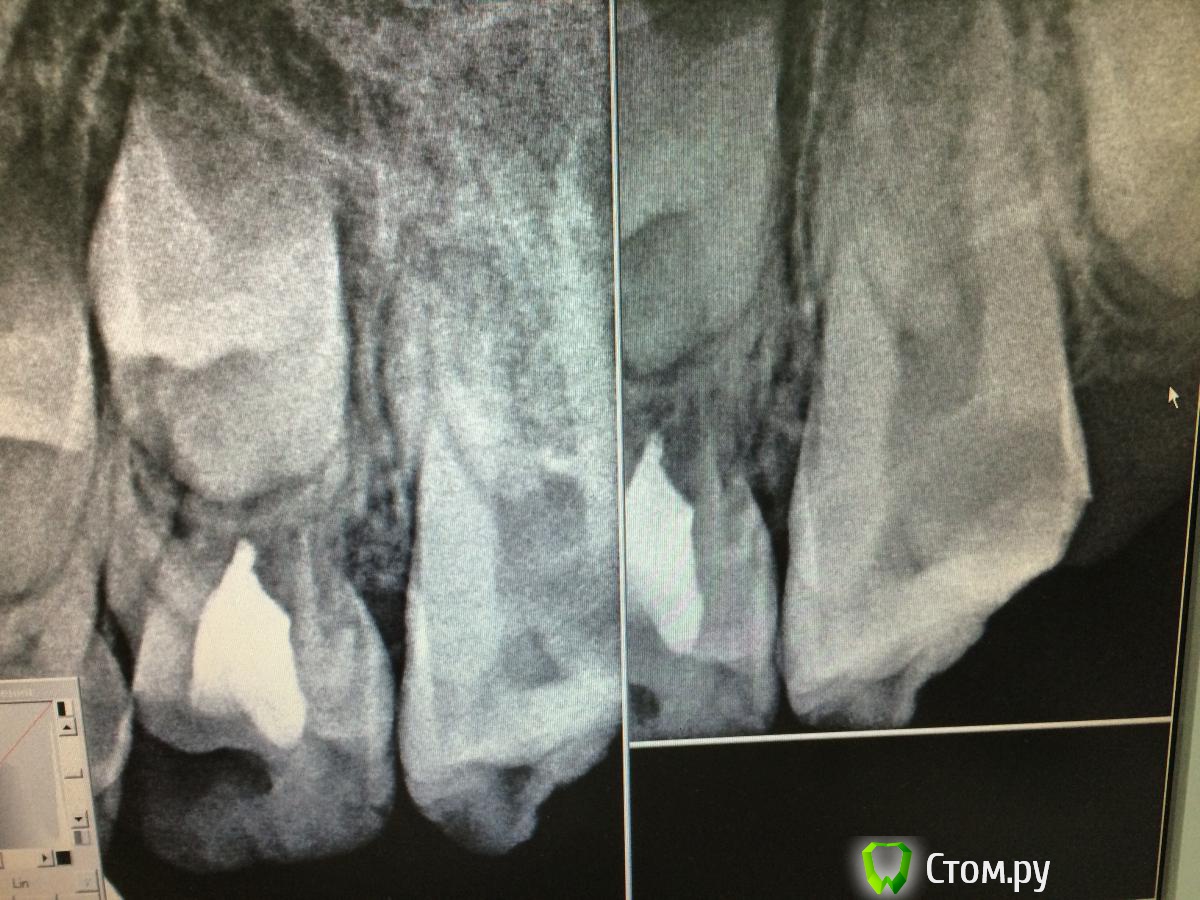

Faya Опубликовано 9 октября, 2014 Поделиться Опубликовано 9 октября, 2014 Доброго времени суток, уважаемые коллеги. Прошу поделиться опытом и мыслями в связи со следующим клиническим случаем. Обратился за помощью мальчик 8 лет - зуб 2.6 - боль, усиливающаяся при накусывании, зуб под временной пломбой. Из анамнеза - 7 суток назад в гос. поликлинике в связи с осложнением кариеса наложен мышьяк под повязку (все со слов папы), боль усиливалась, при повторном обращении вновь наложен мышьяк (вчера). Боль усиливалась...При обращении - конфигурация лица не изменена, по переходной - спокойно, перкуссия слабоболезненна, под временной пломбой, подвижность 1 степени, ИРОПЗ 0,8, разрушен под десневой край на миллиметра 2, что в принципе на мой взгляд не так существенно, т.к. предпологается увеличение клинической высоты при прорезывании (не знаю, права ли). На рентгенограмме (забыла сфотографировать, при возможности добавлю) - сообщение кариозной полости с полостью зуба, корни - раструб. Что сделано - анестезия, восстановление стенок, коффердам, удаление распада, получен гной, мед. обработка 2% хлоргексидин (парканом мыть побоялась), на устья рыхло ватный шарик с жидко замешанным пульпотеком (применяю при обострении пульпита м/з на несколько дней перед пломбированием каналов, крезофены - пульперилы в м/з и несформированных постоянных, по моему мнению, раздражают периодонт, поэтому решила использовать его) под септопак. Явка через 4 суток. Папа предупрежден о возможных осложнения и исходах, условности лечения. У кого какой был опыт в лечении таких зубов? Может какие советы-рекомендации, т. к. с подобным сталкиваюсь впервые, ранее только приходилось лечить пульпиты несформированных, вела с метапексом до окончания формирования, потом пломбировала латералкой, проблем никогда не было. Какой прогноз в данном случае? Ссылка на комментарий

Faya Опубликовано 11 октября, 2014 Автор Поделиться Опубликовано 11 октября, 2014 Rg Ссылка на комментарий

Faya Опубликовано 11 октября, 2014 Автор Поделиться Опубликовано 11 октября, 2014 Выложите снимок. добавила снимки Ссылка на комментарий